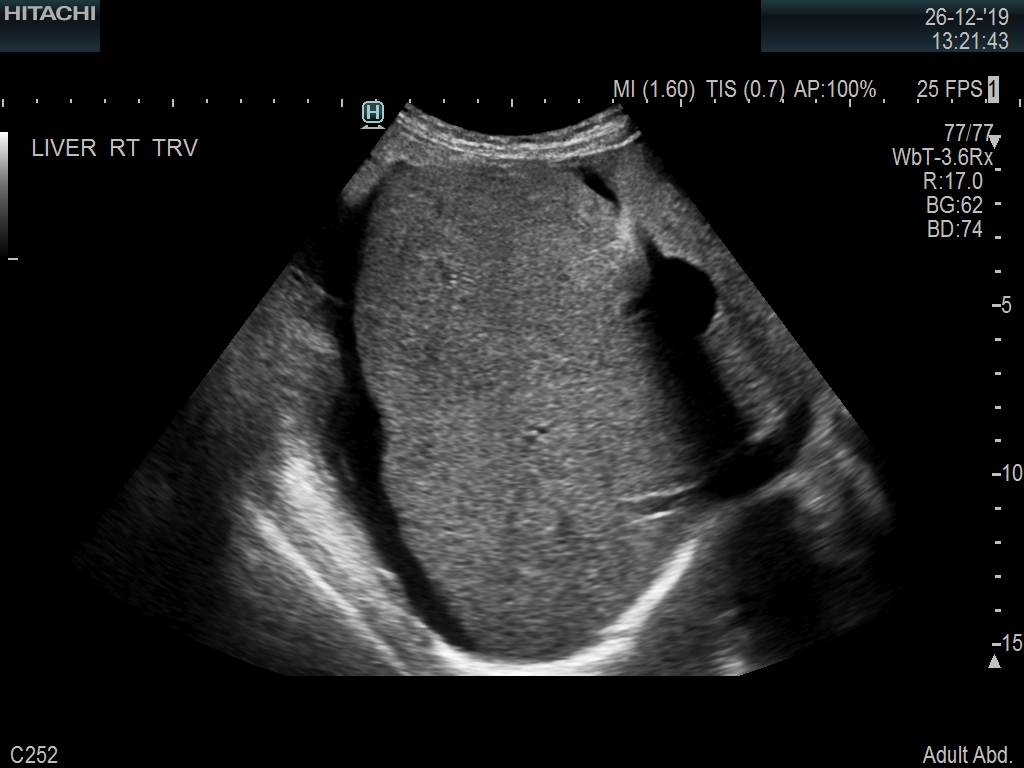

Superior guidance for all applications

Fujifilm Healthcare Americas is committed to designing tools that help surgeons navigate inside the human body and provide the necessary information to immediately make critical surgical decisions.

Fujifilm Healthcare's dedication to Surgeons provides outstanding ultrasound technology, professional support and the specialized tools necessary to best perform comprehensive real-time ultrasound imaging in Breast Surgery, General Surgery, Laparoscopic Surgery, Neurosurgery, Robotic Surgery and Surgical Oncology.

Arietta 70

Recognized for our outstanding image quality, outstanding system reliability and intuitive use of cutting edge technology, Fujifilm Healthcare remains the standard in the field of Surgery.

Learn moreArietta 70

Recognized for our outstanding image quality, outstanding system reliability and intuitive use of cutting edge technology, Fujifilm Healthcare remains the standard in the field of Surgery.